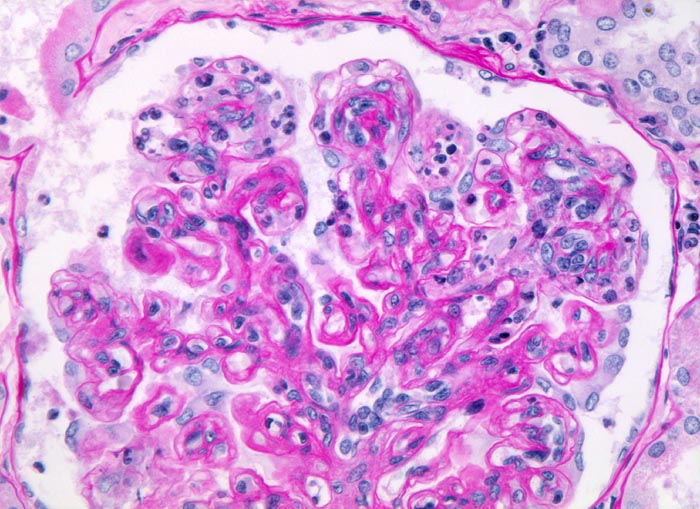

PathoPic – image database / PathoPic ID 4995 - membrano-proliferative Glomerulonephritis Typ I

membrano-proliferative Glomerulonephritis Typ I

Geringe Verbreiterung des Mesangiums mit deutlicher Zellvermehrung (Mesangiumzellkerne überlappen einander, mehr als 3 Mesangiumzellen pro Mesangiumfeld). Die Kapillarschlingen enthalten zahlreiche neutrophile Granulozyten und Monozyten. Die peripheren Basalmembranen sind stellenweise deutlich verdickt bzw. verdoppelt.

Nephrotisches Syndrom, Mikrohämaturie und arterielle Hypertonie. Chronische Hepatitis C.

Der Nachweis von Granulozyten und Monozyten in den Kapillarschlingen und die mesangialen Veränderungen lassen differentialdiagnostisch an eine endokapilläre Glomerulonephritis denken.

Histologie

320